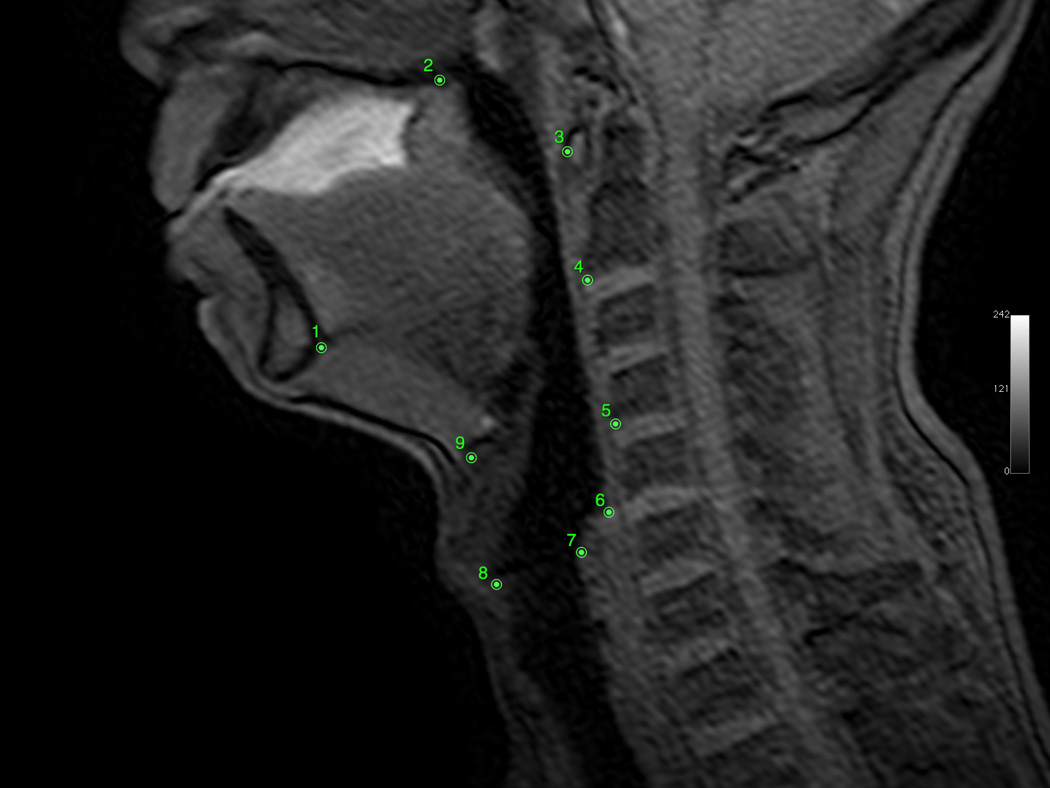

Osirix digital imaging and communication in medicine software was used to produce digital QuicktimeTM videos of dynamic MRI swallows and EPG (www.osirix-viewer.com). Image J image analysis software was used to collect coordinate data of anatomical landmarks from the digital video files (http://rsbweb.nih.gov/ij). From the sagittal image, coordinates of anatomical landmarks tracking the movement of the hyoid, larynx, and pharyngeal walls were collected at rest and at maximum excursion for both the repeated swallowing task and EPG. Minimum and maximum hyolaryngeal excursion among all dynamics (frames) were selected for measurement to ensure that the dynamic range of movement was characterized. Anatomical landmarks included the mandible (inferior mental spine), the posterior edge of the hard palate, the tubercle of the atlas (as a proxy for the styloid process in the lateral view), the anterior inferior edge of C2 and C4, the anterior superior edge of the hyoid, the anterior commissure of the vocal fold, the posterior attachment of the vocal fold, and the most inferior point of the air column in the hypopharynx proximal to the upper esophageal sphincter (UES; see Figure 2, Panels A–D). From coronal images, coordinates of anatomical landmarks mapping pharyngeal wall medialization were measured at the level of the arytenoids for both the repeated swallowing task and EPG (see Figures 3, Panels A–D). Coordinates mapping anatomical landmarks were used to calculate excursion measurements in centimeters for swallowing and EPG, including anterior and superior hyoid movement, hyolaryngeal approximation, laryngeal elevation, and pharyngeal shortening in the midsaggital plane and pharyngeal wall medialization in the coronal plane (see Figure 4). A speech-language pathologist and anatomist measured all subjects independently for interrater reliability.

Figure 2.

A: Sagittal view of minimum hyolaryngeal excursion during EPG. B: Sagittal view of maximum hyolaryngeal excursion during EPG. C: Sagittal view of minimum hyolaryngeal excursion during swallowing. D: Sagittal view of maximum hyolaryngeal excursion during swallowing.

In the current study, the laryngeal elevation measurement approximated the actions of the stylopharyngeus (coordinate 7 represented the distal attachment, and coordinate 3 represented the proximal attachment), and the pharyngeal shortening measurement approximated actions of the palatopharyngeus (coordinate 6 represented the distal attachment, and coordinate 2 represented the proximal attachment). Both the stylopharyngeus and the palatopharyngeus, along with the salpingopharyngeus, are positioned to elevate the larynx and shorten the pharynx (Pearson et al., 2011). The EPG elicited slightly more pharyngeal shortening compared with swallowing, 1.3 cm compared with 0.96 cm, but this difference was not significant (p = .2).